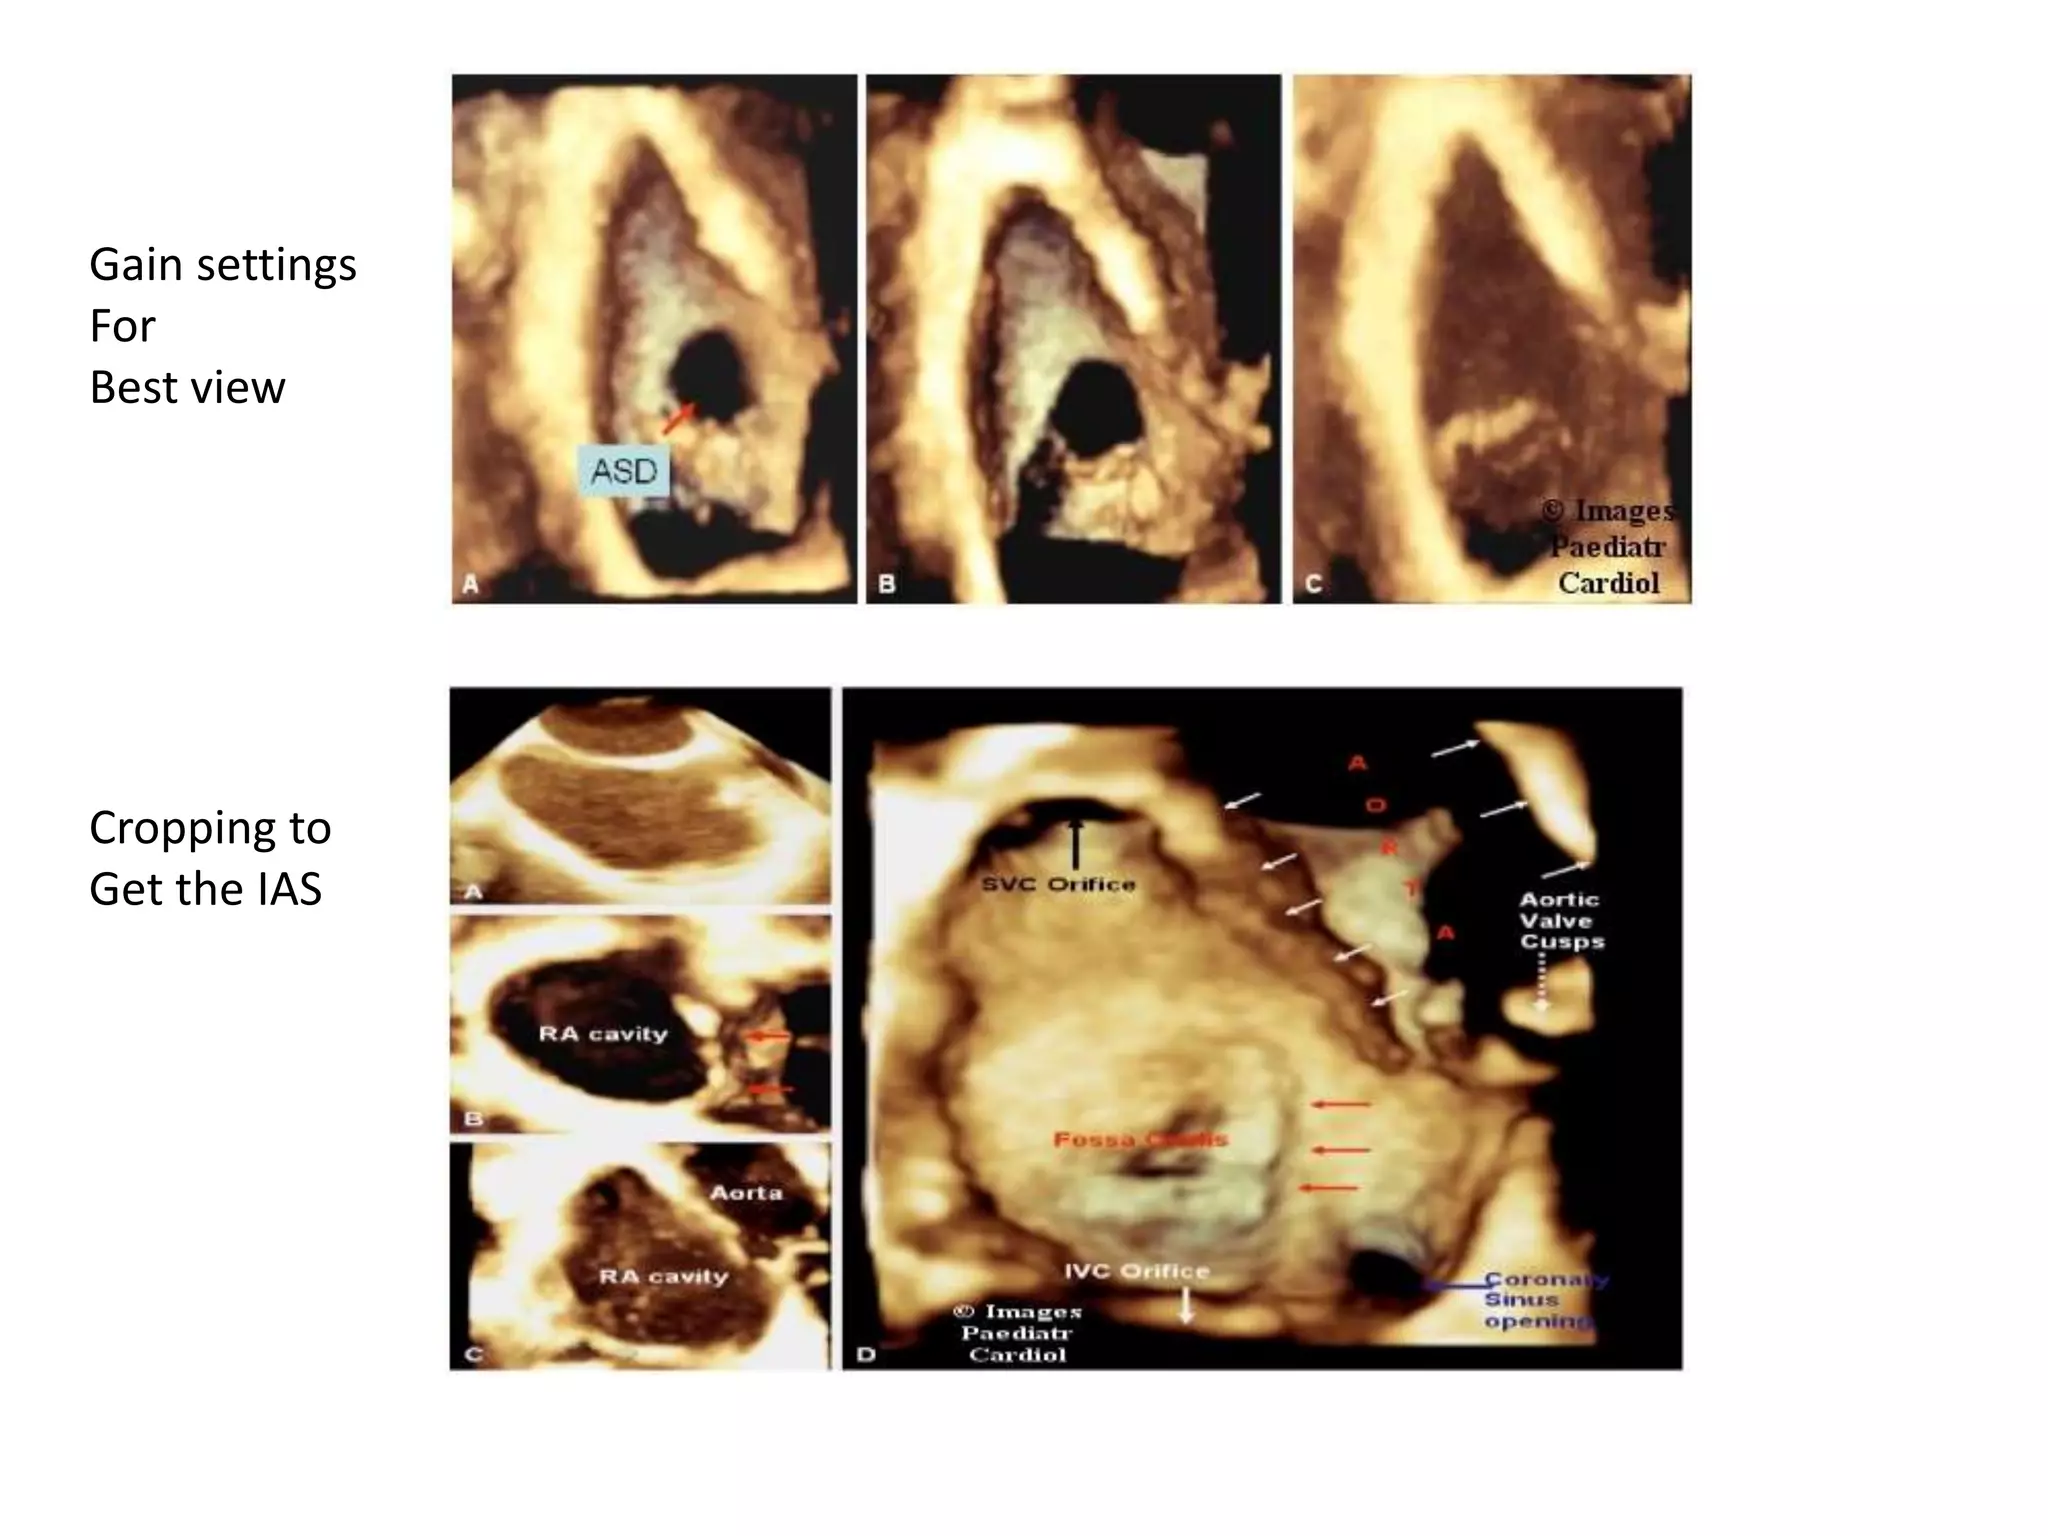

3D ECHO

• Matrix transducers – pyramid shaped volumes

• Full volume 3D dataset in 4-7 cardiac cycles

• Ideal window is the mid esophageal basal long

axis (bicaval view)

• Subcostal 4c view- enface septum

• Low parasternal 4c view case of suboptimal

windows

• 3D tee overcomes 3D TTE if suboptimal windows

• Real-time 3D imaging demonstrates the

changing shape of the ASD during a cardiac

cycle, with maximum size in diastole

• As we take the Bicaval view structures – we

first remove the right atrial free wall .

• Images are taken with suspended respiration

and ECG gating with optimal gain settings

• Low gain – drop outs and high gain – blurring

of structural details

Gain settings

For

Best view

Cropping to

Get the IAS